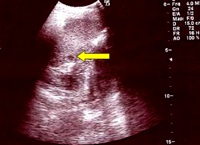

Si decide di eseguire l�ecografia addominale che a livello della milza evidenzia plurime e diffuse piccole zone ipoecogene (Figura 2). All'ilo epatico e in sede periportale evidenza di alcuni linfonodi ovalari, con diametro compreso entro 2 cm. Nella norma il parenchima epatico.

Figura 2. Ecografia Splenica. Milza con ecostruttura disomogenea per la presenza di plurime e diffuse areole nodulari ipoecogene, del diametro compreso tra 8 e 15 mm di non univoca interpretazione (foci flogistici?).

Nel caso di un interessamento epatico e/o splenico pu� non esserci necessariamente un interessamento linfonodale e i pazienti sono indagati per febbre di origine sconosciuta (con sintomi spesso modesti, senza movimento degli enzimi epatici e senza obiettivit� di epatosplenomegalia), in cui vi � riscontro all'ecografia addominale di lesioni ipoecogene nel fegato e/o nella milza (granulomatosi epato-splenica da Bartonella). Dal punto di vista istologico si tratta appunto di granulomi necrotizzanti stellati.

- Il riscontro di un fegato e/o una milza �impallinati� alla indagine ecografica in un contesto come quello descritto, devono fare sospettare una diagnosi possibile, a �colpo d�occhio�, di infezione sistemica con lesioni granulomatose da Bartonella, senza procedere con altre indagini strumentali.